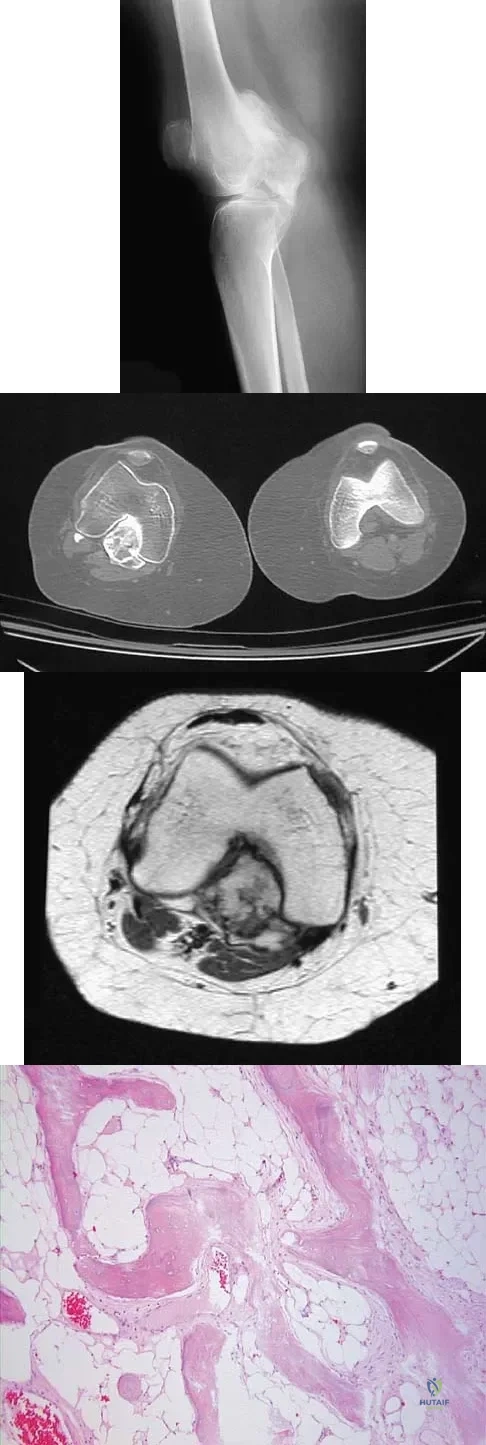

Question 720High Yield

A 16-year-old girl has had painless swelling in her posterior left arm for the past 4 months. A radiograph, MRI scans, and an incisional biopsy specimen are shown in Figures 43a through 43d. What is the cytogenetic translocation most commonly associated with this tumor?

Explanation

This is a case of synovial sarcoma. The radiograph shows some soft-tissue swelling in the upper arm. The MRI scans show a lesion that has increased signal on T2-weighted images and low signal on T1-weighted images. There is a suggestion of a large cystic component to this lesion. The pathology shows a biphasic population of cells, a spindle cell component, and an epithelioid component. Up to 20% of synovial cell sarcomas have areas of cyst formation. The most common cytogenetic translocation with synovial cell sarcoma is X; 18. The 11; 22 translocation is most commonly associated with Ewing's sarcomas; the 12; 22 translocation is most commonly associated with clear cell sarcomas; the 2; 13 translocation is most commonly associated with alveolar rhabdomyosarcomas, and the 12; 16 translocation is most commonly associated with myxoid liposarcomas. Kawai A, Woodruff J, Healey JH, et al: SYT-SSX gene fusion as a determinant of morphology and prognosis in synovial sarcoma. New Engl J Med 1998;338:153-160.